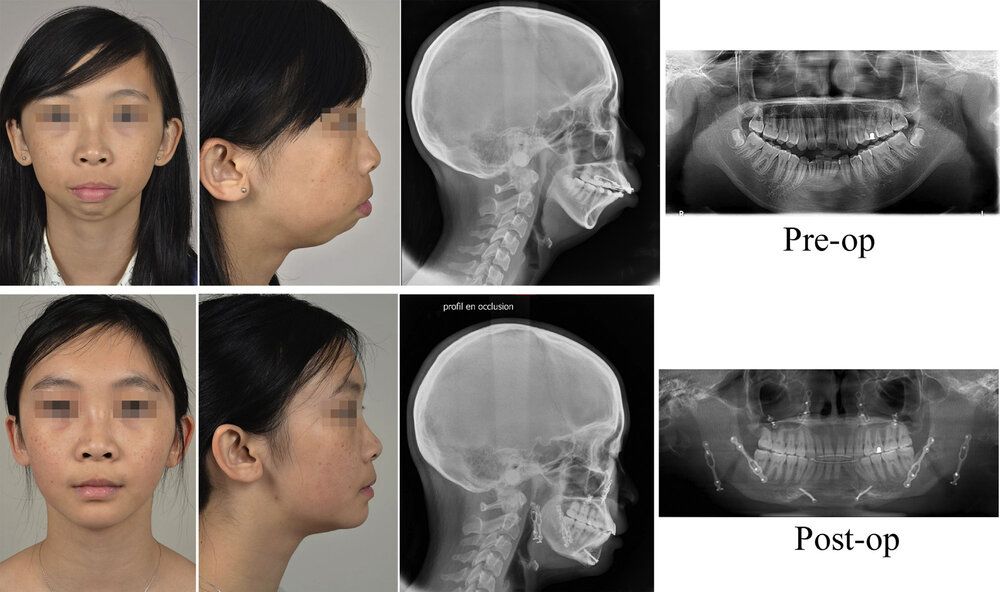

Fig.5. Case 2. Treatment outcomes at 1 year postoperatively. Frontal and profile photographs, profileX-ray and orthopantomogram in preoperative time (top) and at 1 year (bottom).

Fig. 6. Case 3. Treatment outcomes at 2 years postoperatively. Frontal and profile photographs, profileX-ray and orthopantomogram in preoperative time (top) and at 2 years (bottom).